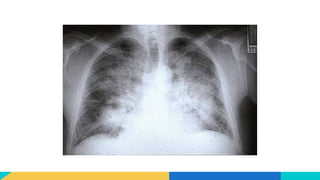

A la Radiothorax

• Peut être normale : en cas d’OAP débutant

• Opacités diffuses bilatérales en ailes de papillon

• Lignes B de Kerley : correspondent à un épaississement des septas

interlobulaires, évoquant un envahissement interstitiel.

• Cardiomégalie

A la Radiothorax •Peut être normale : en cas d’OAP débutant • Opacités diffuses bilatérales en ailes de papillon • Lignes B de Kerley : correspondent à un épaississement des septas interlobulaires, évoquant un envahissement interstitiel. • Cardiomégalie